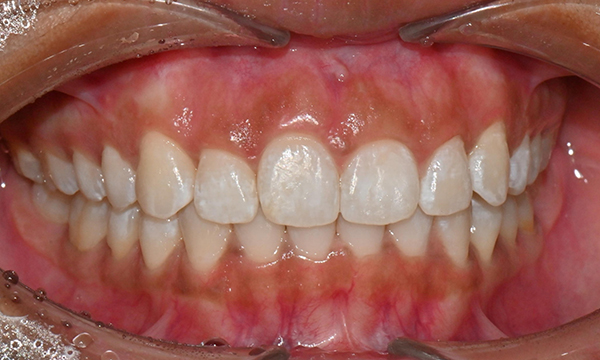

교정 마무리 후 사진 (2025.8)

교정 마무리 후 사진으로 위아래 치아 배열이 개선되었고 공간이 모두 닫혔습니다. 위아래 앞니가 깊게 물리는 과개교합도 처음에 비하여 많이 개선되었습니다. 다만 아래 작은 어금니 배열로 인하여 왼쪽 어금니 교합은 아직 완벽하지 않은 상태로, 추후 본국으로 돌아가서 자료를 transfer 해드려서 이어서 치료를 받기로 하셨습니다.

위 오른쪽 앞니의 경우 초진시에도 틀어져있던 부위의 잇몸이 내려가 있었으므로, 치아가 배열되면 좌우 잇몸 높이가 맞지 않을 것임을 미리 고지시켜드렸었고, 추후 치은성형술로 잇몸 높이를 맞추는 것이 심미적으로 더 보기 좋을 것임을 추천드렸습니다.

약 4개월의 기간 동안 처음부터 마무리까지 총 5번의 내원으로 교정치료가 마무리 되었으며, 위아래 앞니 고정식 유지장치 및 Vivera 유지장치를 착용 후 출국하셨습니다.